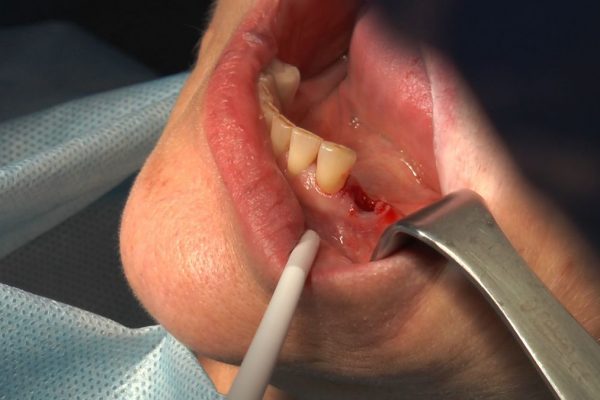

W ostatni weekend czerwca 2018 roku kursanci II Sezonu Preludium Implantologii odbyli piątą, finałową sesję, która w całości podporządkowana była praktyce. W ciągu dwóch dni zabiegowych Lekarze uczestniczący w szkoleniu przeprowadzili szereg zabiegów pod kierunkiem dr n.med. Violetty Szycik. Wszczepili 17 implantów oraz przeprowadzili ekstrakcje i zabiegi regeneracyjne kości. Zabiegi były wykonywane także w sedacji dożylnej z udziałem specjalisty anestezjologii i intensywnej terapii dr Jolanty Grzybowskiej. Preludium implantologii to nowy program edukacyjny dla adeptów implantologii stomatologicznej, którego celem jest wprowadzenie do implantologii poprzez pozyskanie wiedzy w szerokim zakresie i uwzględnieniem szczegółów mających decydujące znaczenie dla powodzenia leczenia implantologicznego. Ale tak jak wszystkie szkolenia w Instytucie Vivadental, w tym wiodące Practiculum Implantologii, zorientowane jest na praktyce i samodzielnym wykonywaniu zabiegów pod kierunkiem Mentora. To najlepsza edukacja w medycynie zabiegowej, a zarazem najlepszy start do implantologii.